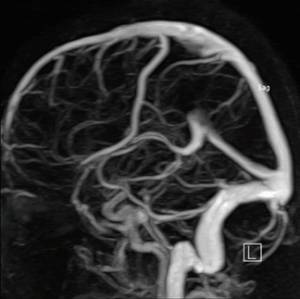

Проверка сосудов мозга с помощью ангиографии для диагностики заболеваний

Эта процедура проводится для определения источника кровотечения, а также при подозрении на наличие опухолей в головном мозге, сужений, тромбов или аневризм сосудов, которые могут вызывать нарушения в мозговом кровообращении. Ангиография позволяет обнаружить чрезмерную извитость сосудов или аномалии в их структуре.

Врачи отмечают, что ангиография сосудов мозга является важным инструментом в диагностике различных заболеваний. Этот метод позволяет визуализировать кровеносные сосуды, выявляя аномалии, такие как аневризмы, стенозы и тромбы. Специалисты подчеркивают, что ранняя диагностика этих состояний может значительно повысить шансы на успешное лечение и предотвратить серьезные осложнения, включая инсульт.

Эти снимки демонстрируют различные фазы кровообращения: капиллярную, артериальную и венозную. Современные медицинские технологии позволяют получать послойные изображения, которые затем обрабатываются с помощью специализированных компьютерных программ для создания трехмерной модели.